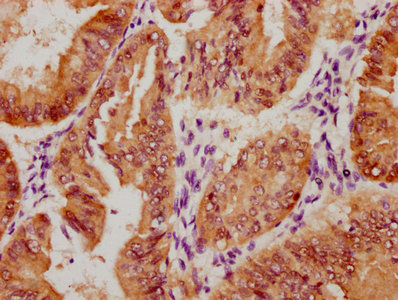

The image on the left is immunohistochemistry of paraffin-embedded Human thyroid cancer tissue using CSB-PA051152(CYP2D6 Antibody) at dilution 1/30, on the right is treated with synthetic peptide. (Original magnification: ×200)